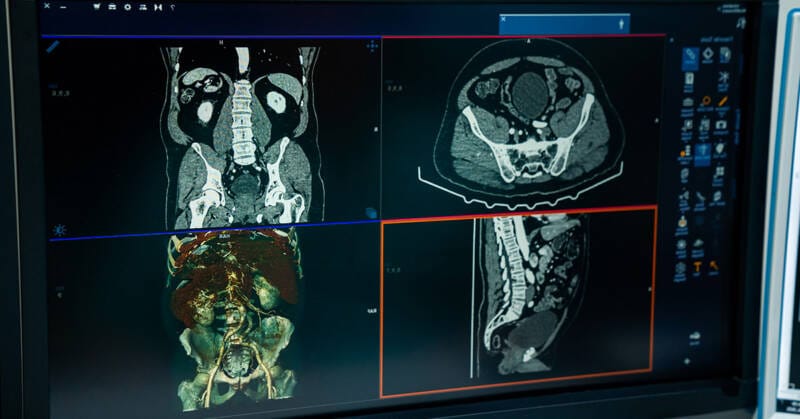

Do ponto de vista tecnológico, as soluções mais maduras baseiam‑se em redes neurais profundas treinadas com grandes bases de imagens. Elas geram heatmaps, pontuações de probabilidade e relatórios estruturados, passíveis de integração ao visualizador DICOM ou ao sistema de gestão da UPA. Além disso, tecnologias de pós‑processamento, supressão óssea, redução de ruído, super‑resolução e realce de contraste, aumentam a legibilidade e podem elevar a sensibilidade da leitura humana e automatizada. Importa distinguir dois usos: (a) apoio à interpretação (assistência ao clínico) e (b) triagem automatizada com substituição parcial de laudo. A opção impacta requisitos regulatórios, fluxos de trabalho e responsabilidades clínicas.

A adoção de ferramentas de inteligência artificial (IA) para apoiar a interpretação de radiografias torácicas persegue dois objetivos centrais: elevar a acurácia diagnóstica em cenários com escassez de especialistas e acelerar decisões clínicas em urgências. Em unidades de pronto atendimento (UPAs), onde muitas vezes quem interpreta o raio‑X não é radiologista, os algoritmos funcionam como “segundo par de olhos”, sinalizando achados relevantes e ajudando a priorizar casos. Essa triagem é especialmente valiosa em redes regionais, como a de Ribeirão Preto, nas quais o fluxo entre UPAs, hospitais de referência e centros de imagem determina o tempo de atendimento e a necessidade de transferências.